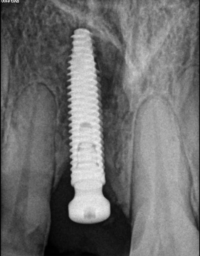

Periodoncia